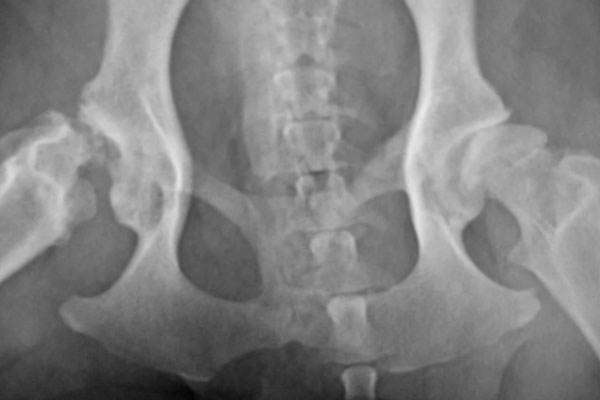

Hunter, a one-year-old yellow Labrador Retriever, first came to Newkirk Family Veterinarians for a second opinion on his hips in July of 2010. He was barely able to walk.

Radiographs indicated a full luxation of the right hip with a very shallow socket.

The left hip was subluxated and had a shallow socket also, but not as severely so. The owners had been told that a total hip replacement needed to be done on both hips, at a cost of about $4000 per hip. They could not afford that and had heard of Dr. Newkirks’ alternative methods for hip dysplasia and chose to come.